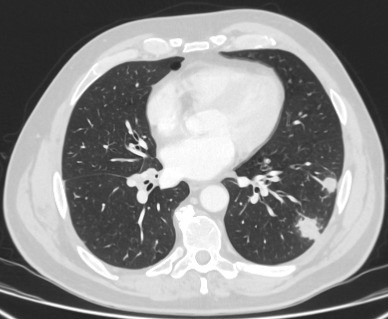

Computed tomography (CT) showing examples of malignant perifissural nodules. Note the spiculated edge of the nodules and the evident retraction of the adjacent fissure. Both resection tissue analyses confirmed adenocarcinoma of lung

From the collection of Dr George Tsaknis, MD, PhD, FRCP(London), MRQA, MAcadMEd, PGCert; used with permission